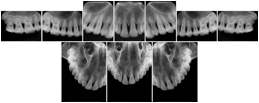

Table OO.1.1-1 shows structured display standard templates, where Viewset ID is based on the Japanese Society for Oral and Maxillofacial Radiology (JSOMR) classification provided by JIRA (Japan Medical Imaging and Radiological Systems Industries Association, www.jira-net.or.jp). Expected or typical teeth to be imaged location, region and designation codes are based on ISO 3950-2010, Dentistry - Designation system for teeth and areas of the oral cavity. For all the hanging protocols listed in OO.1.1-1, the value to use for Hanging Protocol Creator (0072,0008) is "JSOMR" and the value to use for Hanging Protocol Name (0072,0002) does not include "JSOMR" (e.g., "DL-S001A", not "JSOMR DL-S001A").